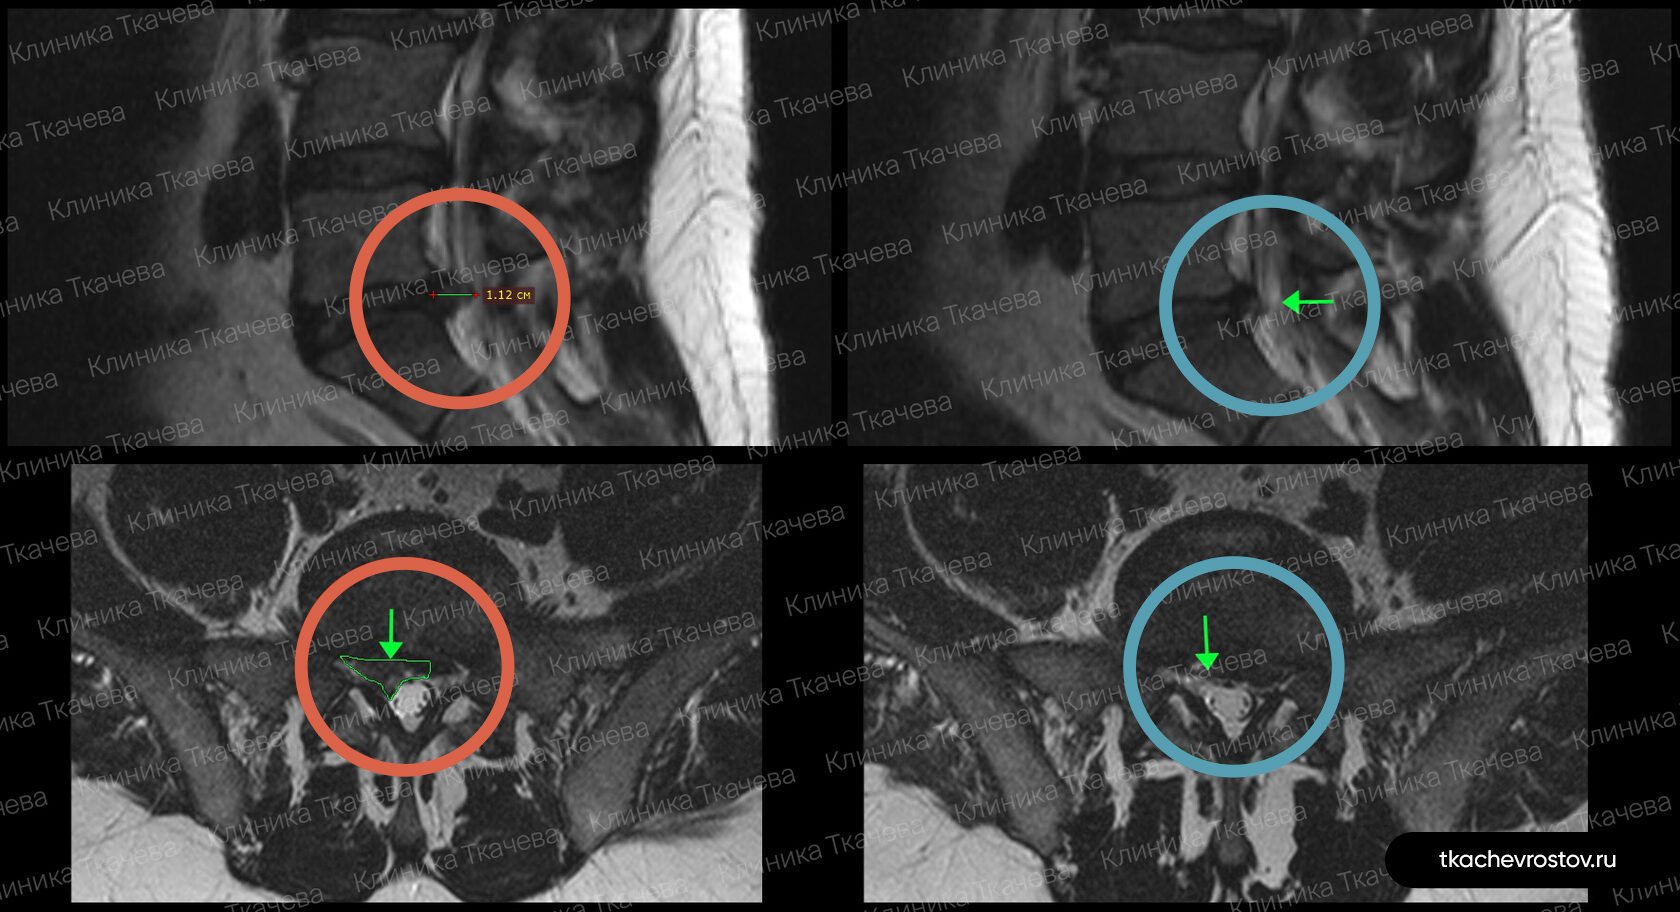

Грыжа в поясничном отделе L4-L5

Женщина. Грыжа в сегменте L4-L5 9 мм х 2 см. Невролог направлял на операцию, нейрохирург пугал отказом всех возможных систем жизнеобеспечения.

ДО:

- Боль в спине

- Онемение в левой ноге

- Снижение бытовой и социальной активности

ПОСЛЕ 1 курса:

✓ Наступила полная резорбция грыжи

✓ Наступило улучшения общего состояния.

ПОСЛЕ 2 курса:

✓ На 2022 всё стабильно.

Лечение грыжи заняло 5 месяцев. Было проведено 2 курса лечения.